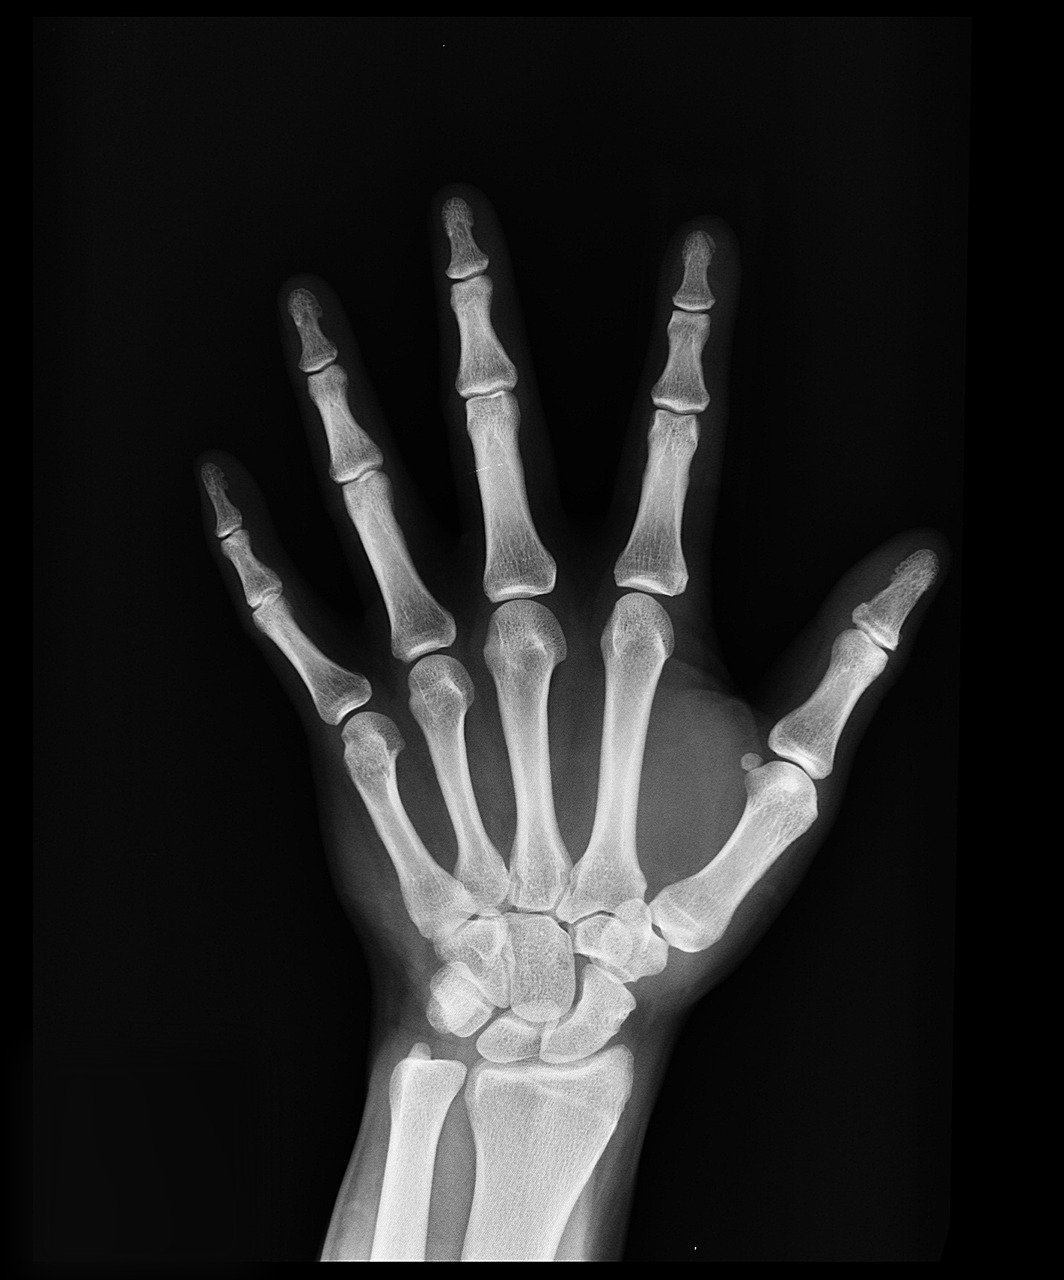

I to prawda — aż 99% wapnia w Twoim organizmie magazynowane jest w kościach i zębach, pełniąc funkcję biologicznego rusztowania, jak podaje amerykański Narodowy Instytut Zdrowia (NIH).